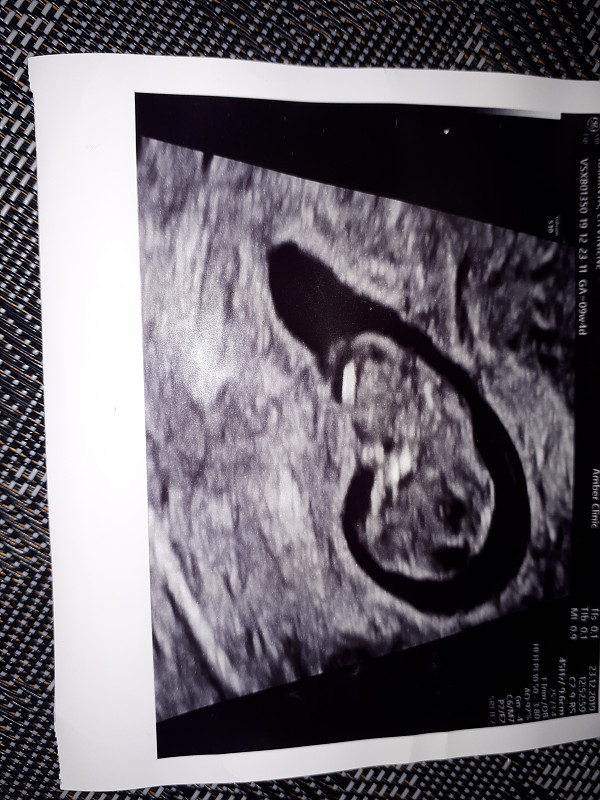

As tai startavau su Ivf, spontaniskai gavosi, bet tikiuosi taip buvo lemta